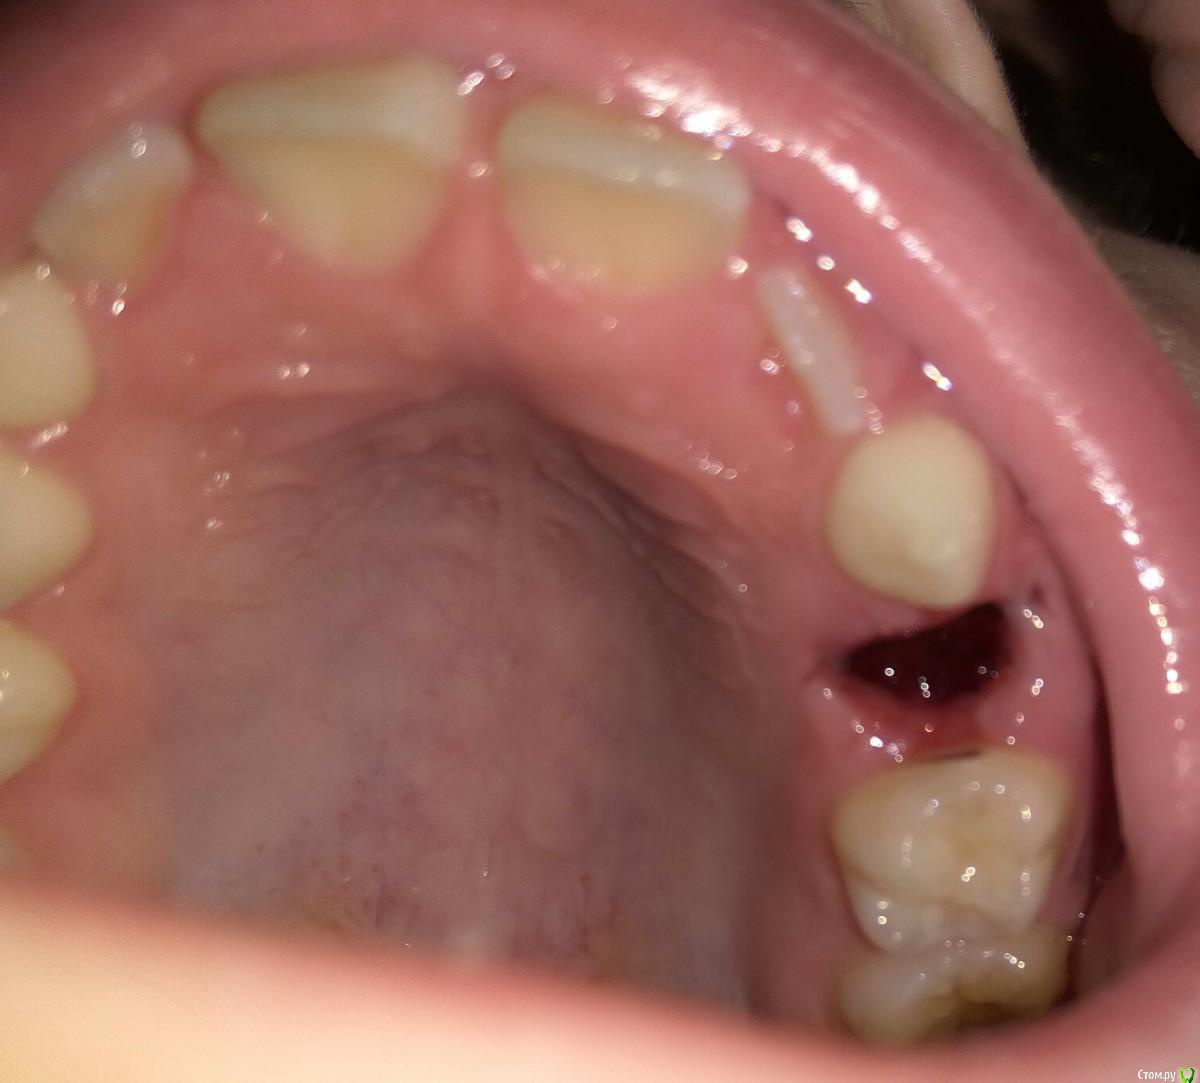

ANTL Опубликовано 11 июня, 2016 Автор Поделиться Опубликовано 11 июня, 2016 Сколько лет ребенку? Покажите фото во рту Ребенку семь с половиной лет. Приложил фото ранки во рту. Ссылка на комментарий

red_butler Опубликовано 11 июня, 2016 Поделиться Опубликовано 11 июня, 2016 Зуб то молочный, но зачем удалили не понял. Rg делали? Ссылка на комментарий

Brigita Опубликовано 11 июня, 2016 Поделиться Опубликовано 11 июня, 2016 ну теперь то уж не вернешь.До постоянного далеко еще, как минимум два года Ссылка на комментарий

Yana guapa Опубликовано 26 июня, 2016 Поделиться Опубликовано 26 июня, 2016 Ребенку семь с половиной лет. Приложил фото ранки во рту. 5.jpg6.jpgна молочной пятерке кариес (со стороны отсутствующего зуба), можно и нужно полечить , пока в пульпит не превратился и пока вам опять не удалили хороший зуб)) Ссылка на комментарий